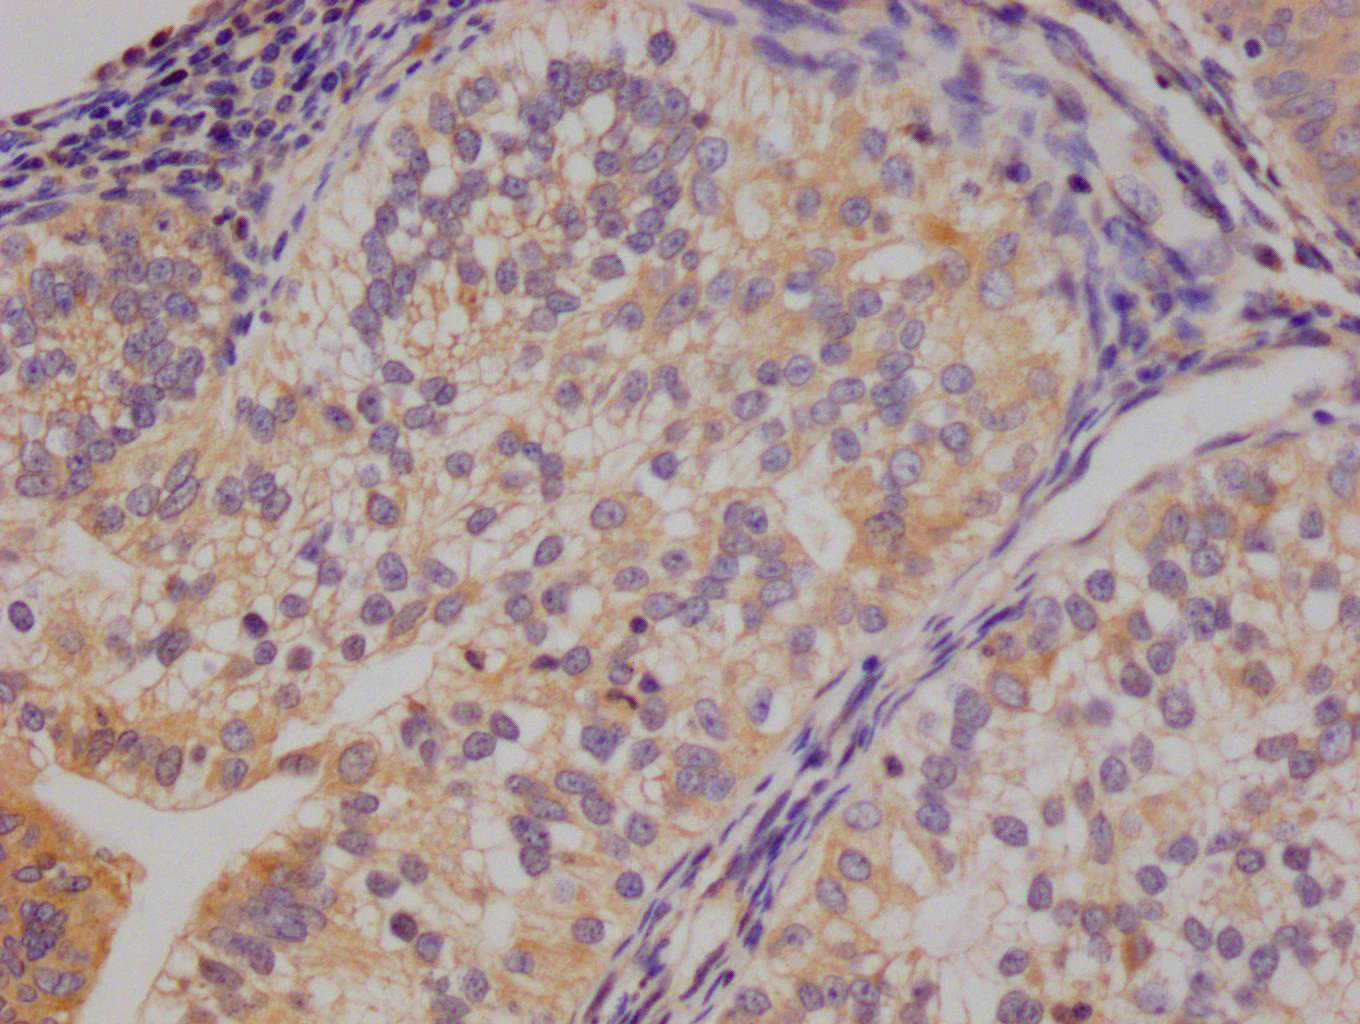

The image on the left is immunohistochemistry of paraffin-embedded Human breast cancer tissue using CSB-PA919263(SPAG4 Antibody) at dilution 1/25, on the right is treated with synthetic peptide. (Original magnification: ×200)

The image on the left is immunohistochemistry of paraffin-embedded Human thyroid cancer tissue using CSB-PA919263(SPAG4 Antibody) at dilution 1/25, on the right is treated with synthetic peptide. (Original magnification: ×200)